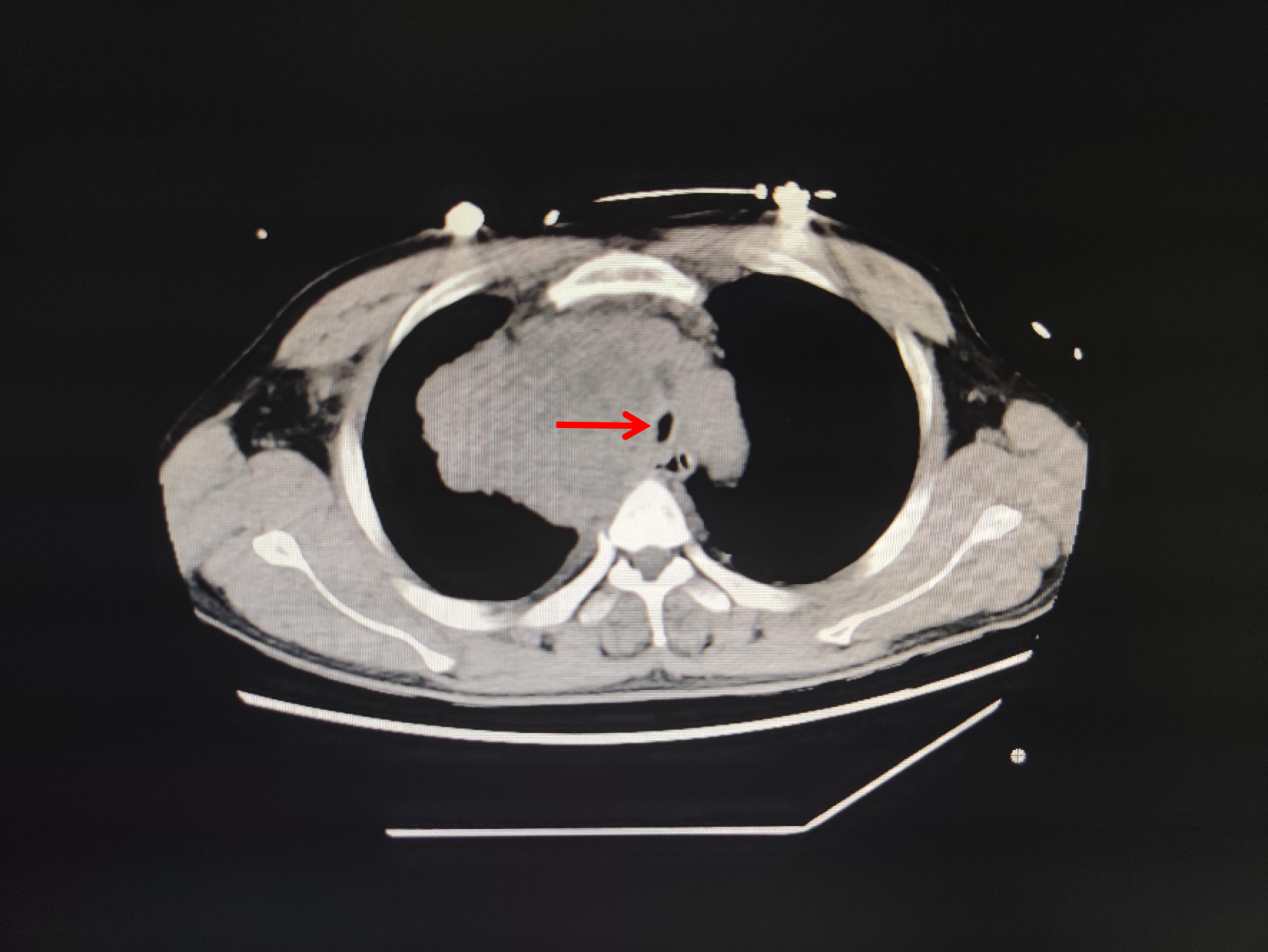

今年57岁的蔡女士,因晚期肺癌住院,肿瘤压迫气管导致气管严重狭窄,住院期间突发呼吸困难,伴烦躁不安、大汗淋漓,紧急行气管插管接呼吸机辅助通气,送ICU抢救。无独有偶,这边ICU医生正在积极抢救蔡女士,那边医院急诊科又打电话说急诊室有一名呼吸困难的患者需要紧急插管。这也是一名肿瘤压迫气管导致气管狭窄的患者,胸部CT可见气管中下段显著性狭窄,患者呼吸困难已近1周,今天突然加重,喘憋、口唇紫绀,ICU翁医生马上紧急予以气管插管,呼吸机持续性辅助通气。

图1.林某某CT 图2.蔡某某CT图片

两名患者行气管插管,接呼吸机辅助呼吸后,病情稍稳定,我院内镜中心呼吸介入治疗团队与ICU治疗团队立即组织病例讨论,行床边气管镜检查,发现两名患者气管均严重狭窄,最窄处不到0.5cm(正常成年人气管直径约1.5cm),一口痰都有可能导致患者严重窒息。在庄武主任和朱坤寿主任支持下,并请有关专家会诊,内镜中心呼吸内镜介入治疗团队经充分论证,认为唯一的治疗方法是——急诊全麻下经硬质气管镜硅酮支架置入术,利用硅酮支架的支撑力,扩张气管,解除呼吸道梗阻,否则患者随时存在生命危险,无法脱离呼吸机。